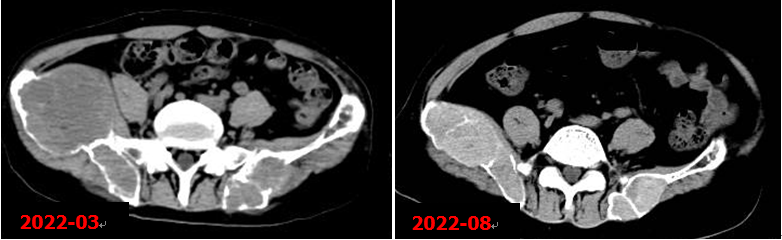

右側(cè)甲狀旁腺腺瘤切除術(shù)后,甲狀旁腺MIBI顯像未見明確病灶組織殘留征象。術(shù)后5個月本院復(fù)查CT示右髂骨病變明顯縮小。